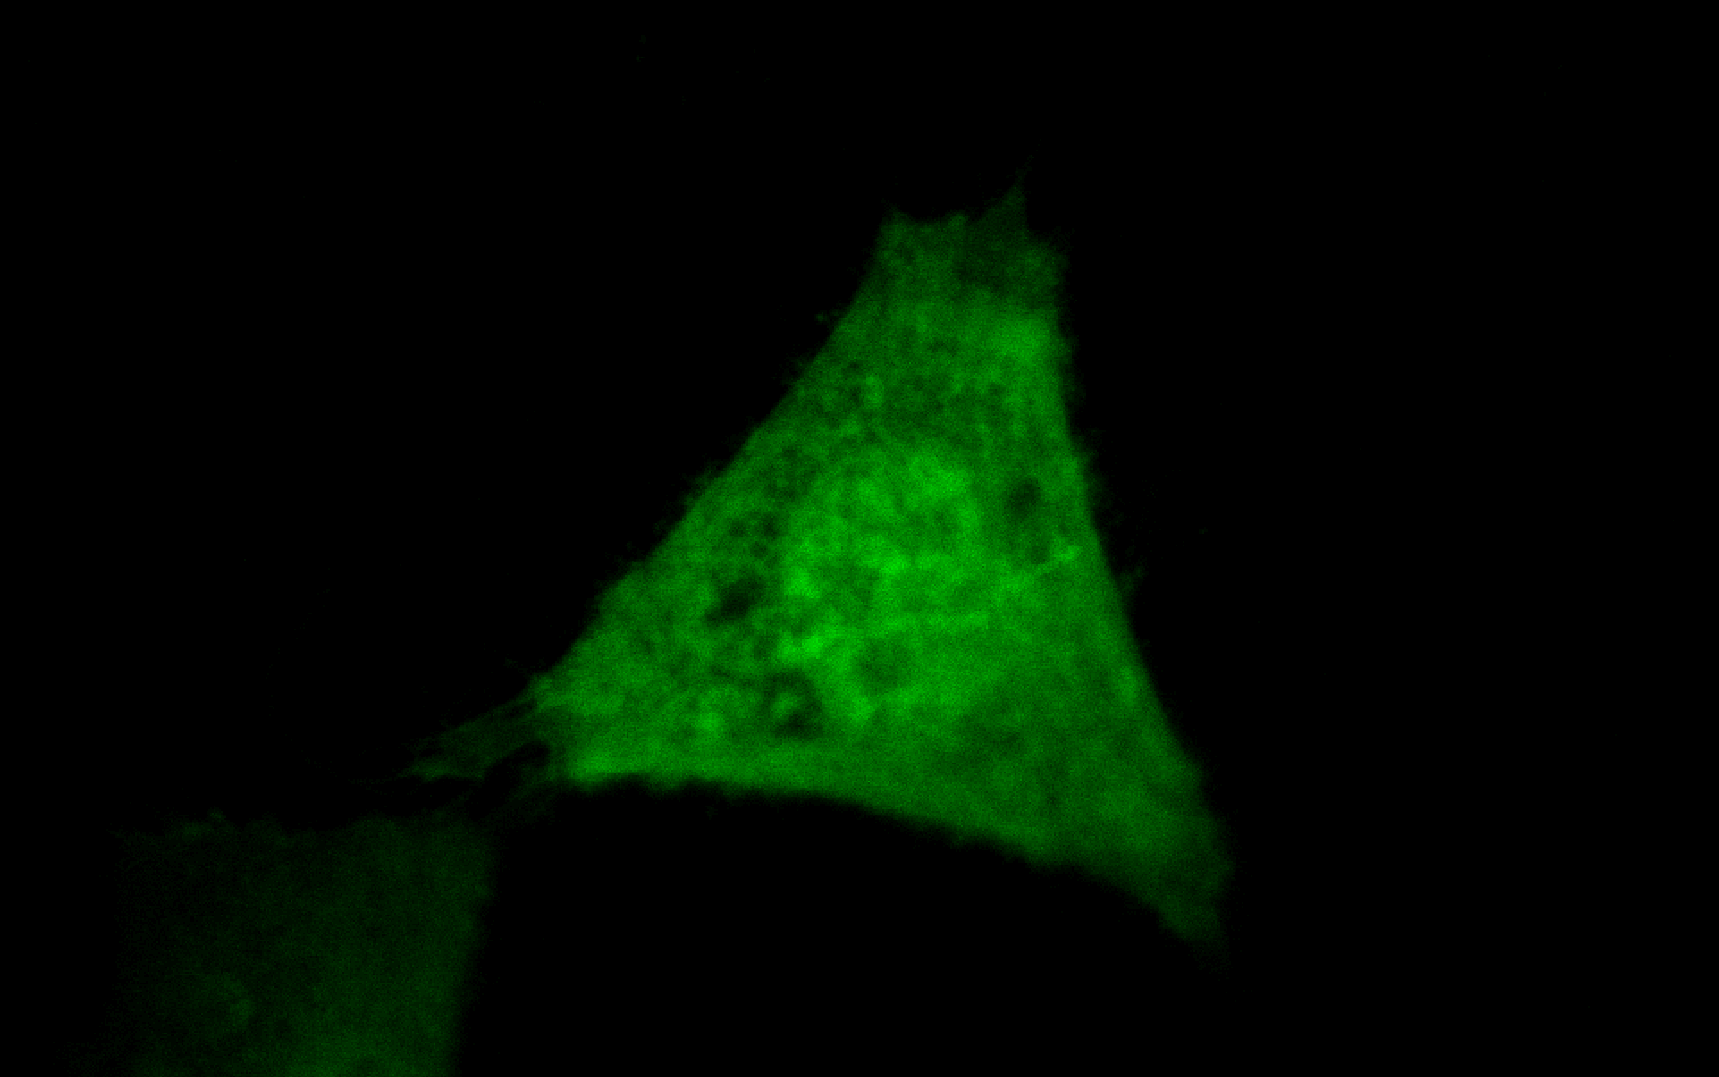

Signalweg Annexin A4 Annexin A4 (ANXA4) ist ein Kalzium- und Phospholipid-bindendes Protein, welches bei humaner Herzinsuffizienz hochreguliert wird. Bislang ist unbekannt, ob dies einen protektiven und kompensatorischen Mechanismus darstellt. In Co-Immunpräzipitations-Experimenten in human emryonic kidney cells (HEK293) konnten wir zeigen, dass es zu einer direkten Interaktion von ANXA4 mit der membrangebundenen Adenylylcyclase 5 (AC5) kommt. Adenylylcyclasen sind essenziell für die reguläre aber auch pathophysiologische Signalantwort von Kardiomyozyten und katalysieren die Umwandlung von Adenosintriphosphat (ATP) zu zyklischem Adenosinmonophosphat (second messenger cAMP). Eine Überexpression von ANXA4 in HEK293 Zellen nach Stimulation ging einher mit einer verminderten cAMP Produktion, wohingegen eine Inaktivierung von ANXA4 in Mäusen einherging mit einer erhöhten cAMP Produktion. Somit fungiert ANXA4 wohl als Inhibitor der AC5.

In Kardiomyozyten gibt es zwei prädominante AC-Isoformen, die AC5 und die AC6. Eine spezifische AC5 Inhibition gilt als eine neue Option zur Behandlung der Herzinsuffizienz mit möglichen Vorteilen gegenüber einer Behandlung mit β-Adrenozeptor-Inhibitoren (β-Blocker). Wir konnten bereits in HEK293 Zellen zeigen, dass ANXA4 über seinen N-Terminus spezifisch nur mit AC5 interagiert und nicht mit AC6. Ein synthetisches Peptid bestehend aus der N-terminalen Sequenz von ANXA4 (A4N1-22) verminderte nach Stimulation ebenfalls die cAMP Produktion in AC5- aber nicht in AC6-exprimierenden HEK293 Zellen. In ANXA4-defizienten Mäusen führte die β-AR Stimulation aufgrund der dort fehlenden AC5 Inhibition zur Erhöhung des L-Typ Kalziumkanal Stroms und zu einer ausgeprägten Aktionspotential-Verlängerung in Kardiomyozyten. Nach Zugabe des synthetischen A41-22 Peptids konnte diese verstärkte Antwort, wahrscheinlich durch die dann verursachte spezifische Inhibition der AC5, wieder aufgehoben werden. ANXA4 inhibiert somit über seine N-terminale Domäne spezifisch AC5 und nicht AC6. Das synthetische A41-22 Peptid (Patentanmeldung „Specific AC5 inhibitor“ PCT/EP2017/076839) könnte somit als spezifischer AC5 Inhibitor einen neuen therapeutischen Ansatz für die Behandlung von AC5-verbundenen Krankheiten darstellen.